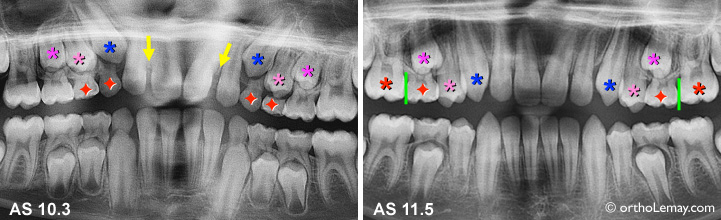

Cas AS

Cas AS : Extractions sélectives (rouge) ayant permis d’améliorer la direction d’éruption des canines (*bleu) et premières prémolaires (*rose pâle) en 14 mois. Ces dents se sont redressées et on fermé les espaces entre les incisives (flèche jaunes) en faisant éruption. L’étape suivante à 11.5 ans serait d’extraire les secondes molaires temporaires (rouge) et de poser un mainteneur d’espace pour éviter la migration vers l’avant des premières molaires permanentes (*rouge).